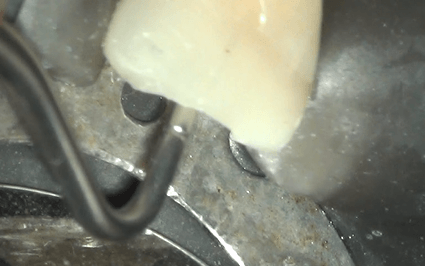

Dus succesvol waren we wel met de kanaalbehandelingen. De afgelopen 8 jaar heeft P. geen pijn meer gehad, tot 2 weken geleden. Er lijkt iets aan de hand met de apex 21. Die apex lijkt iets korter of in ieder geval iets anders dan op de foto’s uit 2006 en 2010. Zou herinfectie een rol hebben kunnen spelen? Ondenkbaar is dat niet. Composiet vullingen lekken vanaf dag 1 en gutta percha kan niet zo goed weerstand bieden tegen lekkage. De foto genomen door de microscoop van het palatinale aspect van element 21 doet vermoeden dat er zeker sprake moet zijn van lekkage.

Aanbrengen van MTA gaat het handigste met behulp van een MTA blok. Daarin zijn kleine gladde groefjes gemaakt waarin een handige assistente een weinig MTA van de juiste consistentie kan smeren. Dat staafje vochtige MTA blijft dan hangen aan een plugger, meestal de dunste Machtou-plugger, en voorzichtig in het kanaal gebracht worden. Daarna voorzichtig en zachtjes aanschuiven. Het streepje op de Machtou-plugger geeft aan dat we 2 millimeter van de terminus zitten, dat geeft enige zekerheid dat MTA op de juiste plaats zit.